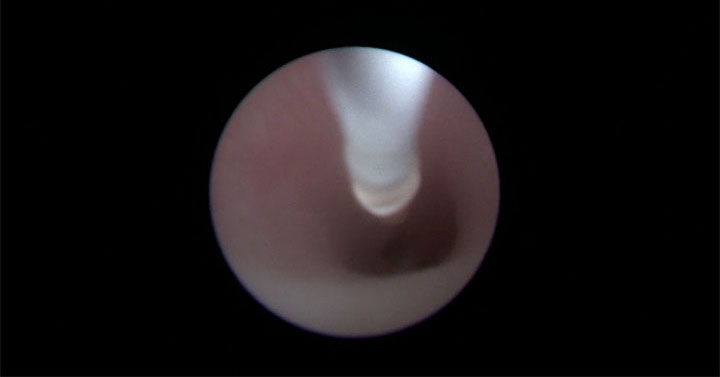

Con la mamma in anestesia locale ed il feto “sedato” con una puntura sulla coscia, è stato inserito un fetoscopio (sonda molto sottile dotata di telecamera a fibre ottiche) nell’addome della gestante. Passando per la bocca del feto (lungo appena 35cm per 1,2kg di peso), è stata raggiunta la trachea dove è stato posizionato e gonfiato un minuscolo palloncino, un “tappo” che blocca la fuoriuscita del liquido normalmente prodotto dal polmone. L’accumulo del fluido all’interno dei polmoni, che nei casi di ernia diaframmatica sono di dimensioni ridotte, li mantiene in espansione e ne favorisce lo sviluppo. Circa un mese prima del parto, il palloncino sarà rimosso con la stessa procedura per permettere al neonato di avere la trachea libera e quindi di respirare normalmente al momento della nascita. A distanza di 10 giorni dall’intervento, i controlli ecografici hanno rilevato un significativo aumento del volume dei polmoni fetali.